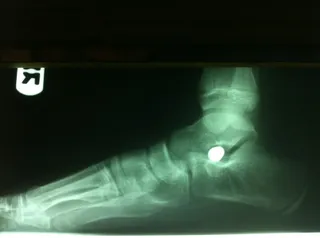

Below are x-rays of a foot pre-operatively (left) where the black line indicates and plantarflexed (downward directed) talus bone and post-surgical repair with a subtalar joint implant and lenthening of the calf muscle which allows the calcaneus (heel bone) to set underneath the talus and the implant keeps the talus from subluxing off the calcaneus and now the talus is more inline with the front of the foot (right).